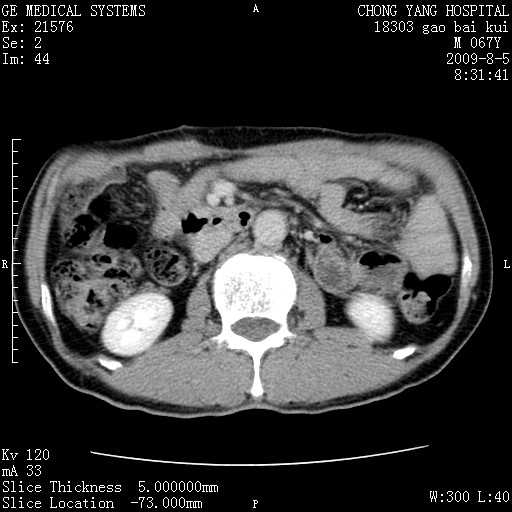

这个也过了,考虑胰腺钩突癌或壶腹癌,不除外胰管粘液乳头瘤伴胰管扩张,肝内胆管积气.

1)考虑胰头癌或壶腹癌并胰管扩张。2)肝外胆管扩张、积气,胆囊影未见;考虑术后改变。3)胃壁增厚?建议必要时行胃镜检查。

虑胰腺钩突癌或壶腹癌,不除外胰管粘液乳头瘤伴胰管扩张,肝内胆管积气.

考虑胰头癌并十二指肠受侵。